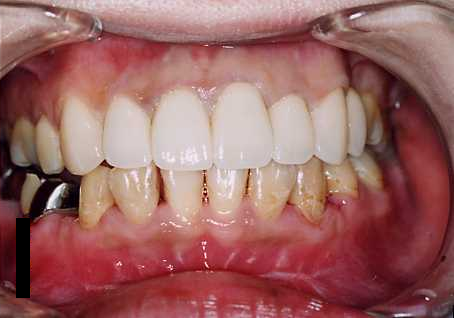

症例 2

| BEFORE | AFTER |

|---|---|